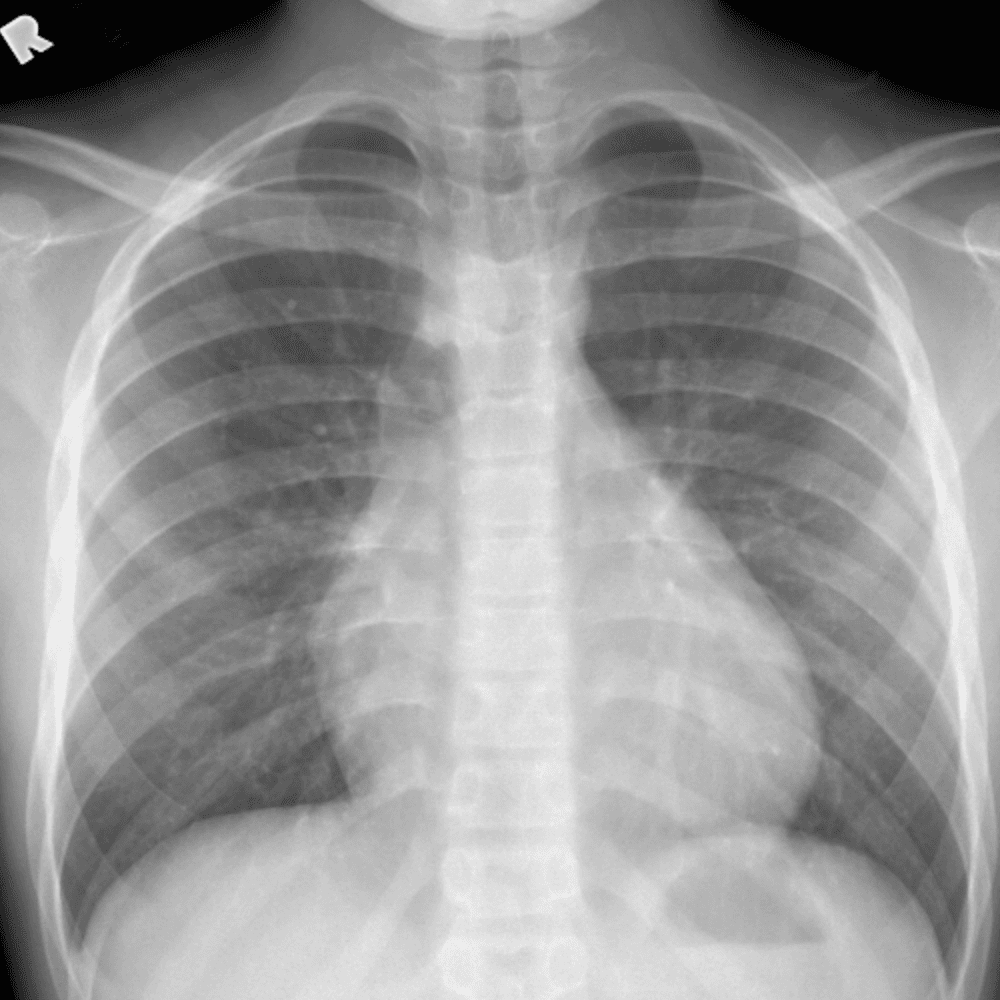

Peds Chest

Practice

Simulates call by including subtle or difficult cases and some normals.

50 cases